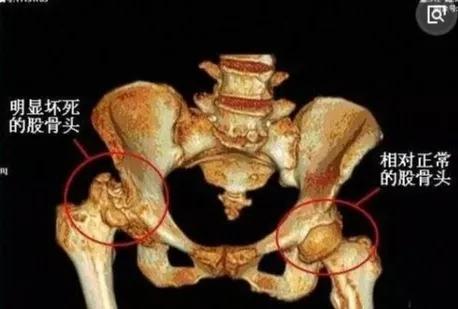

这时拍X光片会看到股骨头内有半月状软骨下断裂,股骨头软骨下骨小梁与软骨分离,股骨头骨皮质断裂、软度蹋陷。